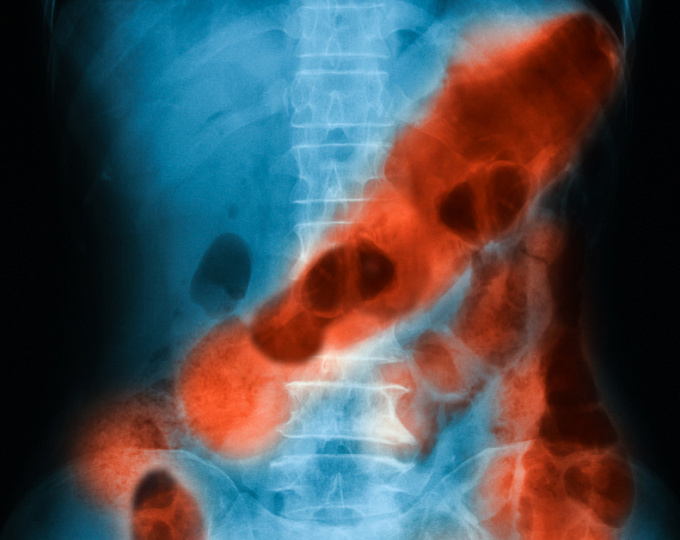

Инструментална диагностика на инфаркт на червата

Ако пациентът няма признаци на перитонит, се извършват инструментални изследвания:

Компютърна томография (КТ)

КТ се предписва най-често при съмнение за мезентериална исхемия. Тя позволява да се изключат други заболявания с подобни симптоми, като остър апендицит , панкреатит, холецистит , остра чревна непроходимост . КТ може да покаже пневматоза (въздушни кисти в чревната стена), както и въздух в порталната вена, фокален оток на чревната стена и оток на мезентериума. При венозна тромбоза КТ може да покаже уголемена мезентериална или портална вена с ясно очертана венозна стена и ниска плътност вътре в съда.

Ангиография

Извършва се, ако компютърната томография (КТ) не успее да установи диагноза и има сериозно съмнение за остра мезентериална исхемия. Диагнозата се потвърждава, ако по време на ангиографията се видят контрастни дефекти и ако стволът и клоновете на мезентериалните артерии не са запълнени с контраст. Това е най-надеждният метод за определяне на наличието и степента на съдова оклузия. Въпреки това, сега се използва все по-рядко, тъй като КТ е нетравматичен и по-достъпен диагностичен метод.

Дуплексен ултразвук

Това помага за оценка на кръвния поток и идентифициране на местоположението на стеснението на съдовете. Може да покаже съсирек или липса на кръвен поток в засегнатите артерии или вени. Но за разлика от ангиографията, това изследване не може да открие съсиреци извън главните артерии.